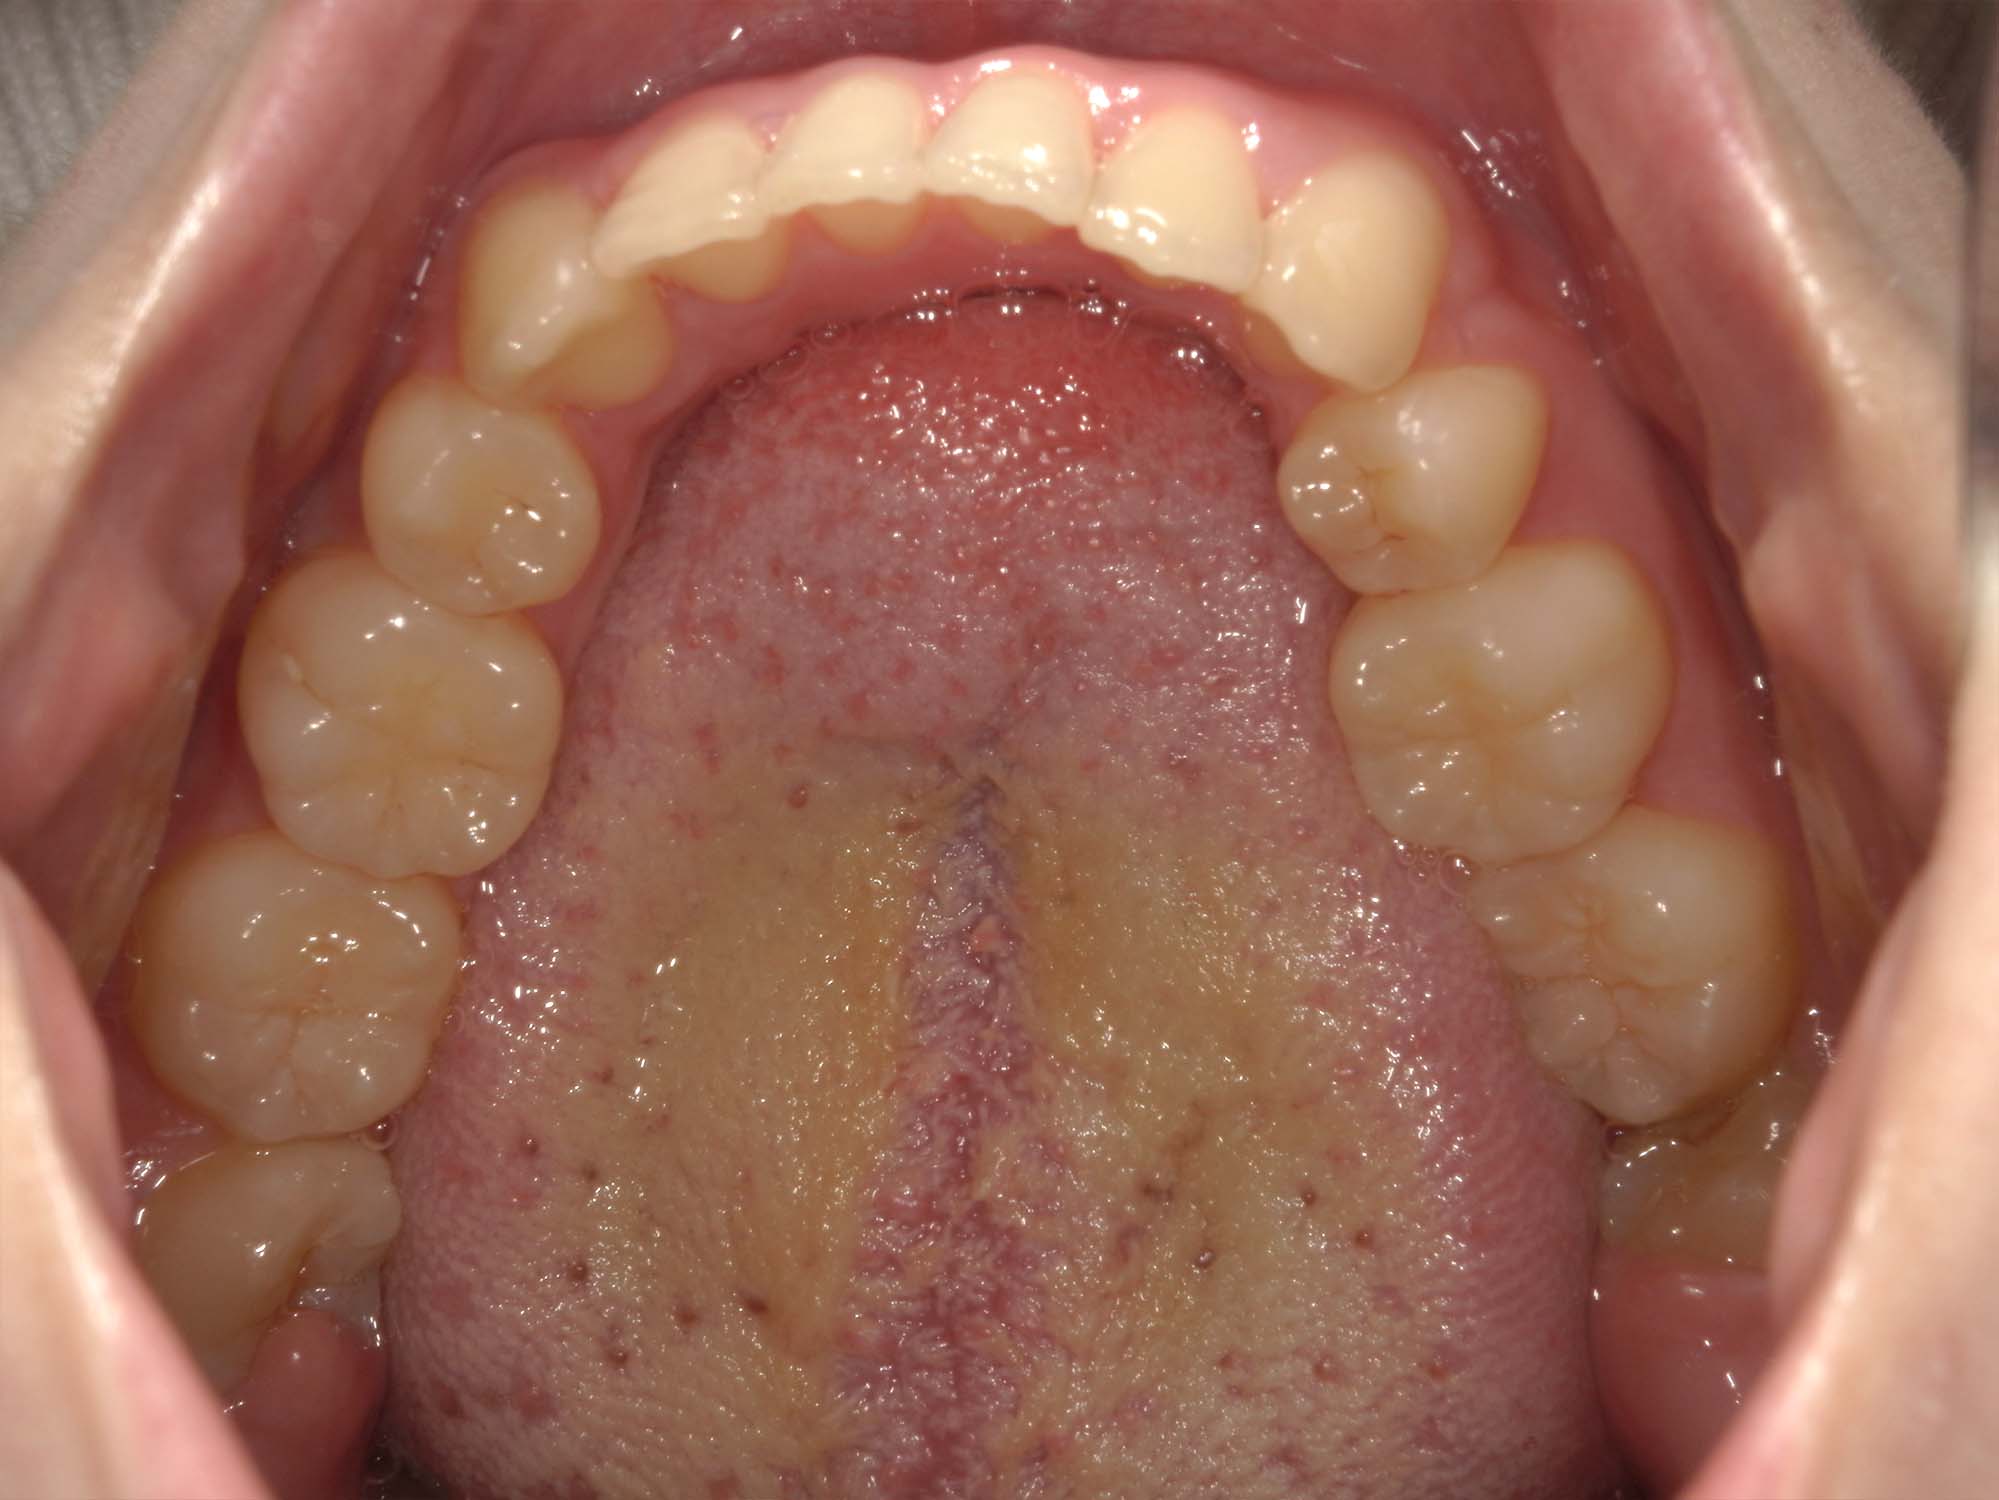

| 年齢・性別 | 25歳の女性 |

|---|---|

| 主訴 | 口元の突出感を気にされて来院された。咬み合わせや審美的な改善を希望されていました。 |

| 治療期間・回数 | 3年6ヶ月・30回 |

| 費用 | 1,000,000円 |